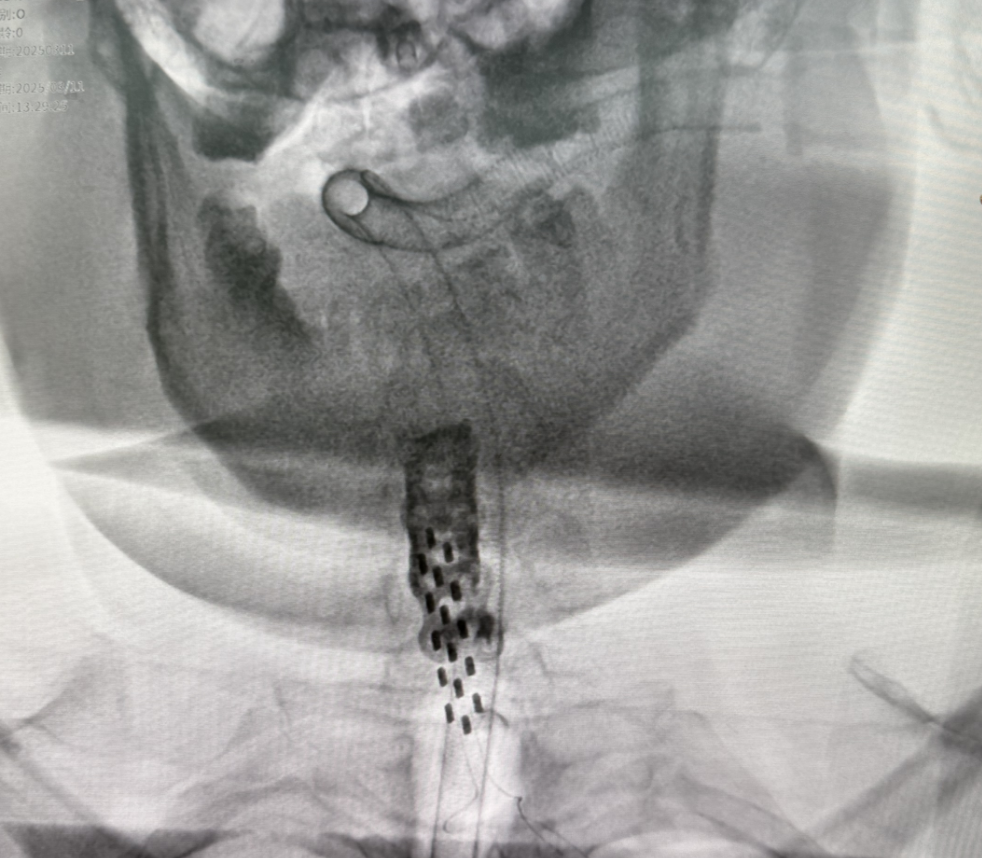

术中精准定位

术中借助三维影像重建和神经电生理评估,为患者量身定制电极植入位置及电刺激参数;

术后通过体外程控设备实时调整脉冲频率、强度等,确保神经信号的高效传导。